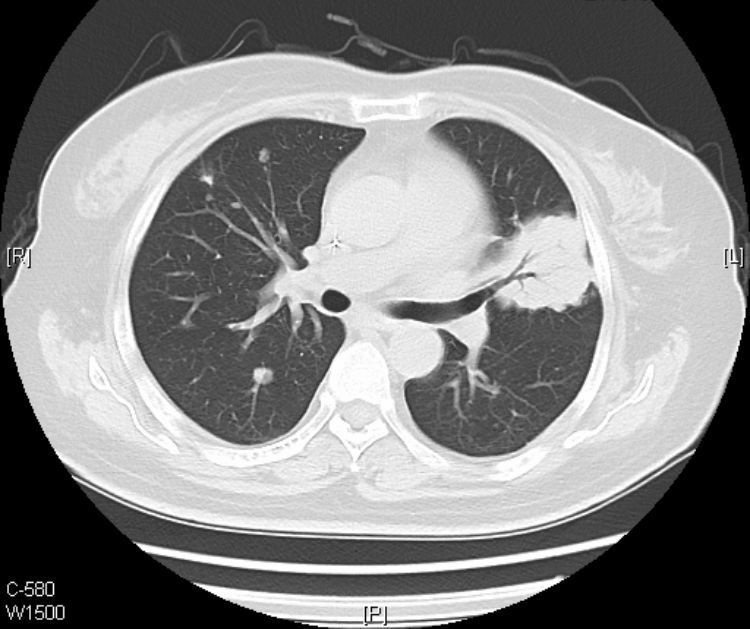

这是一位62岁的小老太,咳嗽咳痰伴低热一个月,伴有白色粘液痰。

胸部平片示重症肺炎表现(2012-7-23),临床伴有II型呼吸衰竭表现。

在影像上,黏液腺癌分两种类型:结节肿块型和肺炎型。

肺炎型的初期常被误诊为肺炎,上图的老太太就属于这个类型。

接着看她往下的CT层面: